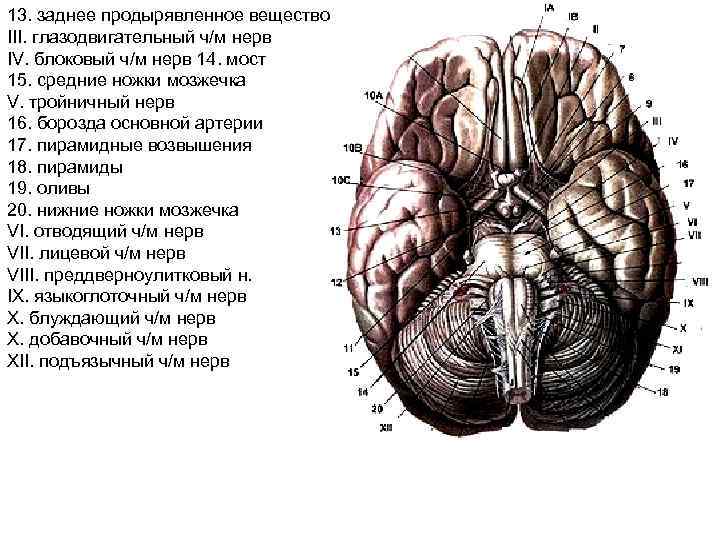

Необычные объекты: Переднее продырявленное вещество